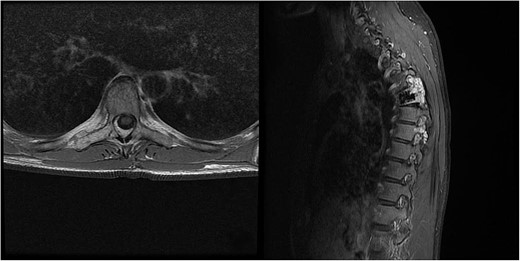

Three and a half years prior to admission to our institution, the patient underwent emergent Th6 vertebroplasty with laminectomy for a radiologically characteristic and histologically confirmed Th6 AVH causing acute thoracic myelopathy with a week-long paresis of the right foot dorsiflexion, performed by another surgeon. A progressive kyphotic deformity of the Th6 vertebrae was observed on radiographic follow-ups, whereby the hypoesthesia on the right anterior thigh persisted (ASIA score D, VAS pain score 7). Follow-up MRI and CT imaging revealed recurrent AVH of the Th6 vertebrae expanding into the spinal canal, leading to newly recognized worsening of myelopathy (Fig. 1). Additionally, a concomitant haemangioma was observed in the right transverse and articular process of Th8 (Fig. 2).

MRI scan of the thoracic spine showing a concomitant haemangioma in the right transverse and articular process of Th8.